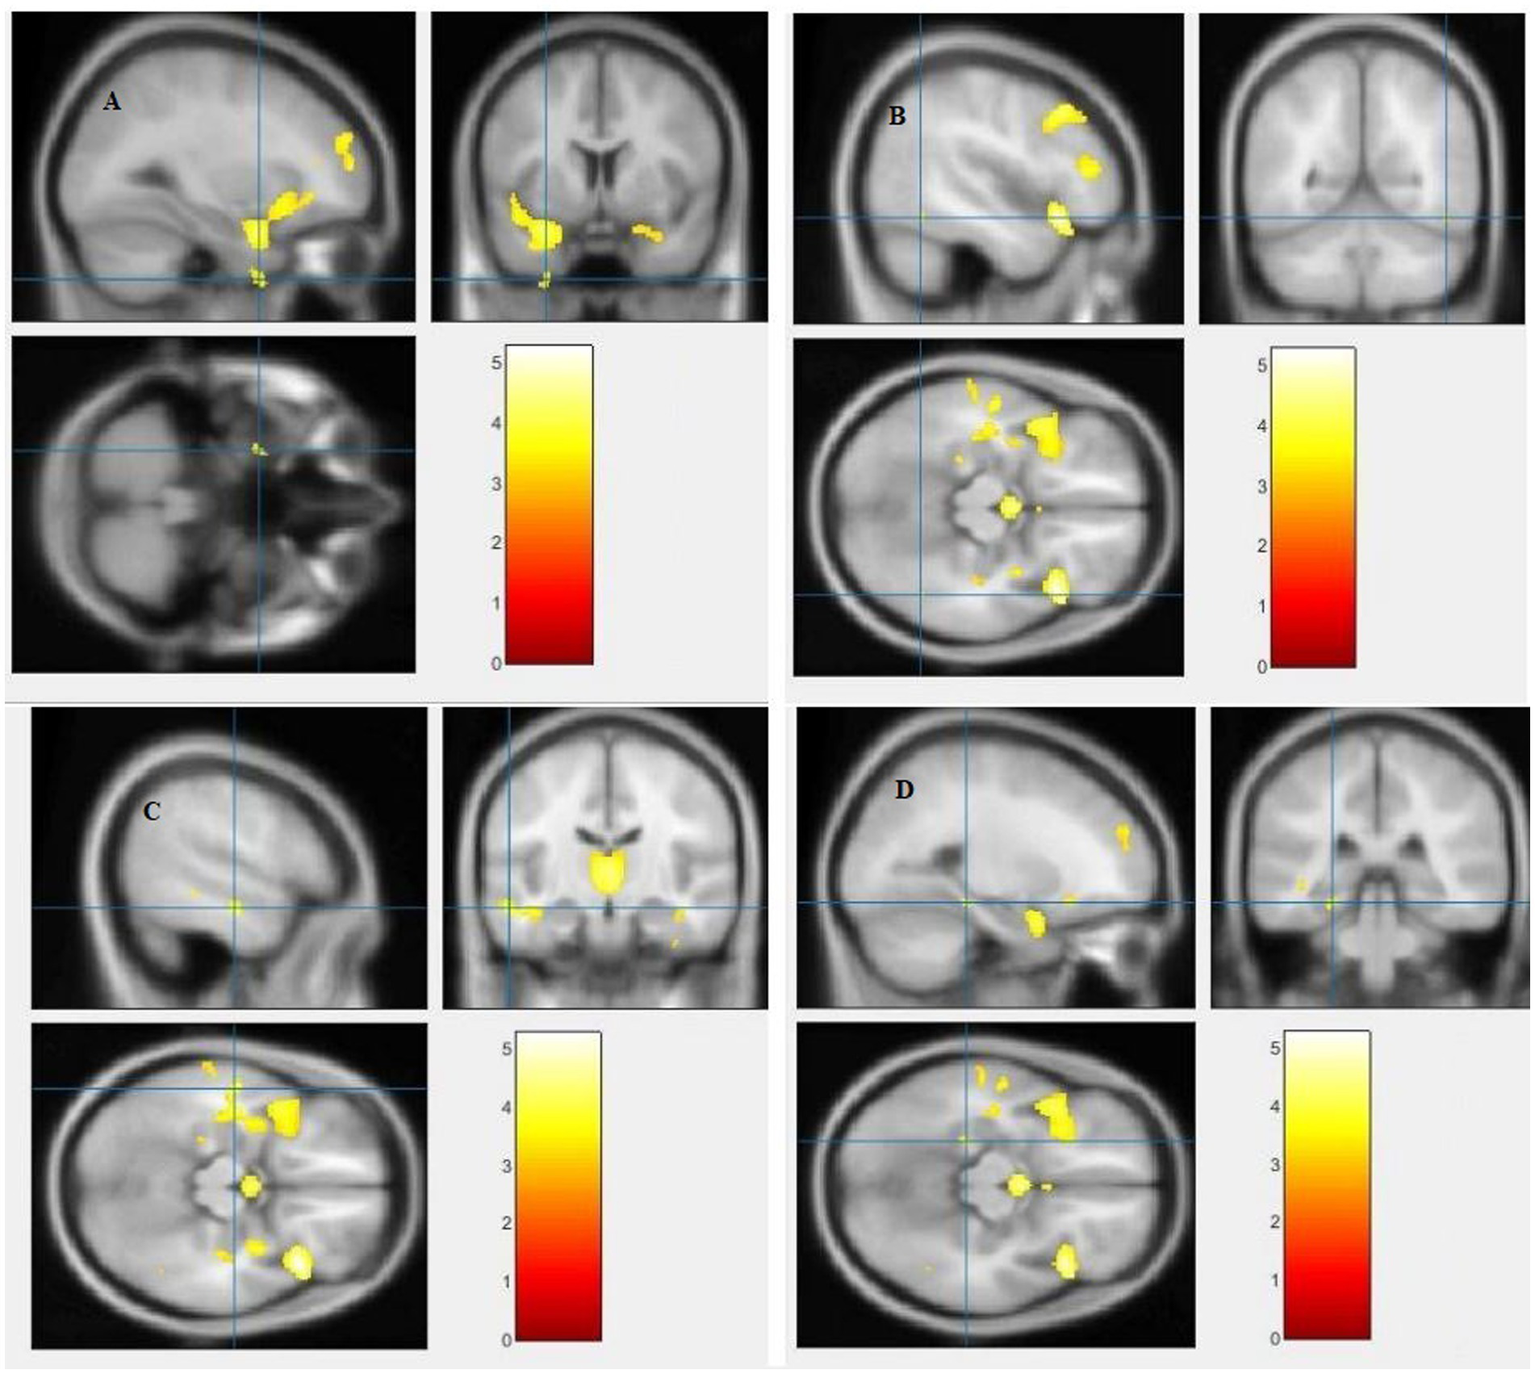

The study used a voxel-by-voxel analysis with family-wise error correction method to compare the gray matter, white matter, and cerebrospinal fluid volumes between schizophrenic patients and healthy controls. The significance level was set at p < 0.05 in a t test and extent threshold K = 100. The results showed significant reductions in gray matter volume in multiple brain regions in schizophrenic patients compared to healthy controls, including the right inferior frontal gyrus, right middle frontal gyrus, right superior frontal gyrus, right subcallosal gyrus, left middle temporal gyrus, left postcentral gyrus, and left cingulate gyrus (Table 3; Figures 2, 3). Moreover, significant reductions in white matter volume were observed in several brain regions in schizophrenic patients, including the left parahippocampal gyrus, left superior temporal gyrus, right fusiform gyrus, left middle temporal gyrus, left inferior frontal gyrus, right inferior frontal gyrus, right sub-gyral, and right middle frontal gyrus (Table 4; Figures 4, 5). White matter plays a critical role in connecting different brain regions and facilitating communication between them. Finally, the analysis revealed that schizophrenic patients had significant increases in cerebrospinal fluid volume in the left third ventricle and left lateral ventricle regions compared to healthy controls (Table 5; Figure 6). Figures 2-6 and Tables 3-5 contain detailed information on the brain regions and peak voxel coordinates.

Figure 2

Voxel-based morphometric analyses identified gray matter (GM) alterations in the Right inferior frontal gyrus (A), Right middle frontal gyrus (B), Right superior frontal gyrus (C) and Right subcallosal gyrus (D), with statistical significance at p < 0.05 and an extent threshold of K = 100 when SZ < HC.

Figure 4

Voxel-based morphometric analyses identified white matter (WM) alterations in the Left inferior frontal gyrus (A), Right inferior frontal gyrus (B), Right sub-gyral (C) and Left middle frontal gyrus (D), with statistical significance at p < 0.05 and an extent threshold of K = 100 when SZ < HC.